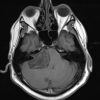

U dây VIII

» Thông tin: Nam giới – 50 tuổi.

» Lâm sàng: Đau đầu + Mất thính giác phải.